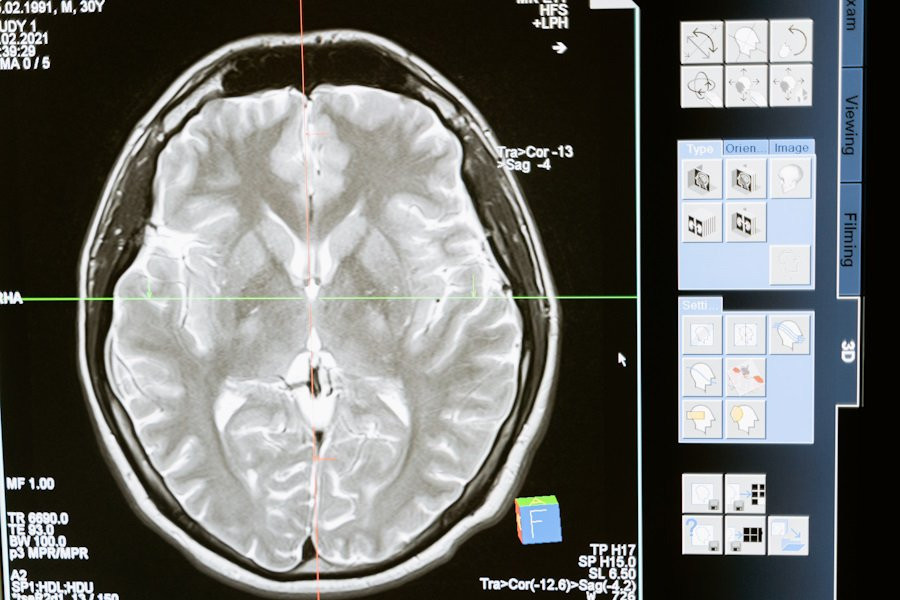

Биохимики из University of Miami объявили о создании нового метода лечения рака, направленного на борьбу как с первичным раком груди, так и с его метастазами, включая те, которые проникают в мозг. Разработанные ими наночастицы могут преодолеть барьер между кровотоком и мозгом, обычно препятствующий многим лекарствам достичь целевых клеток внутри головного мозга, сообщает сайт университета.

Разработанные наночастицы имеют оптимальные размеры и структуру, позволяющие им проникать через гематоэнцефалический барьер, который обычно защищает мозг от многих молекул. Это открывает новые возможности для адресной доставки лекарств в ткани мозга, что позволяет эффективнее лечить как первичные опухоли, так и их метастазы.